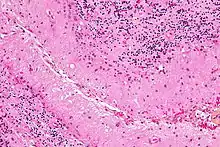

Micrograph showing Bergmann gliosis. H&E stain.

Bergmann glia (also known as radial epithelial cells, Golgi epithelial cells, or radial astrocytes) are unipolar astrocytes derived from radial glia that are intimately associated with Purkinje cells in the cerebellum.[9] Since bergmann glia appear to persist in the cerebellum, and perform many of the roles characteristic of astrocytes, they have also been called "specialized astrocytes."[8] Bergmann glia have multiple radial processes that extend across the molecular layer of the cerebellar cortex and terminate at the pial surface as a bulbous endfoot.[10] Bergmann glial cells assist with the migration of granule cells, guiding the small neurons from the external granular layer down to the internal granular layer along their extensive radial processes.[11][12] Besides their role in early development of the cerebellum, Bergmann glia are also required for synaptic pruning.[13] Following Purkinje cell death induced by CNS injury, Bergmann glia undergo extensive proliferative changes so as to replace lost or damaged tissue in a process known as gliosis.[14][15]